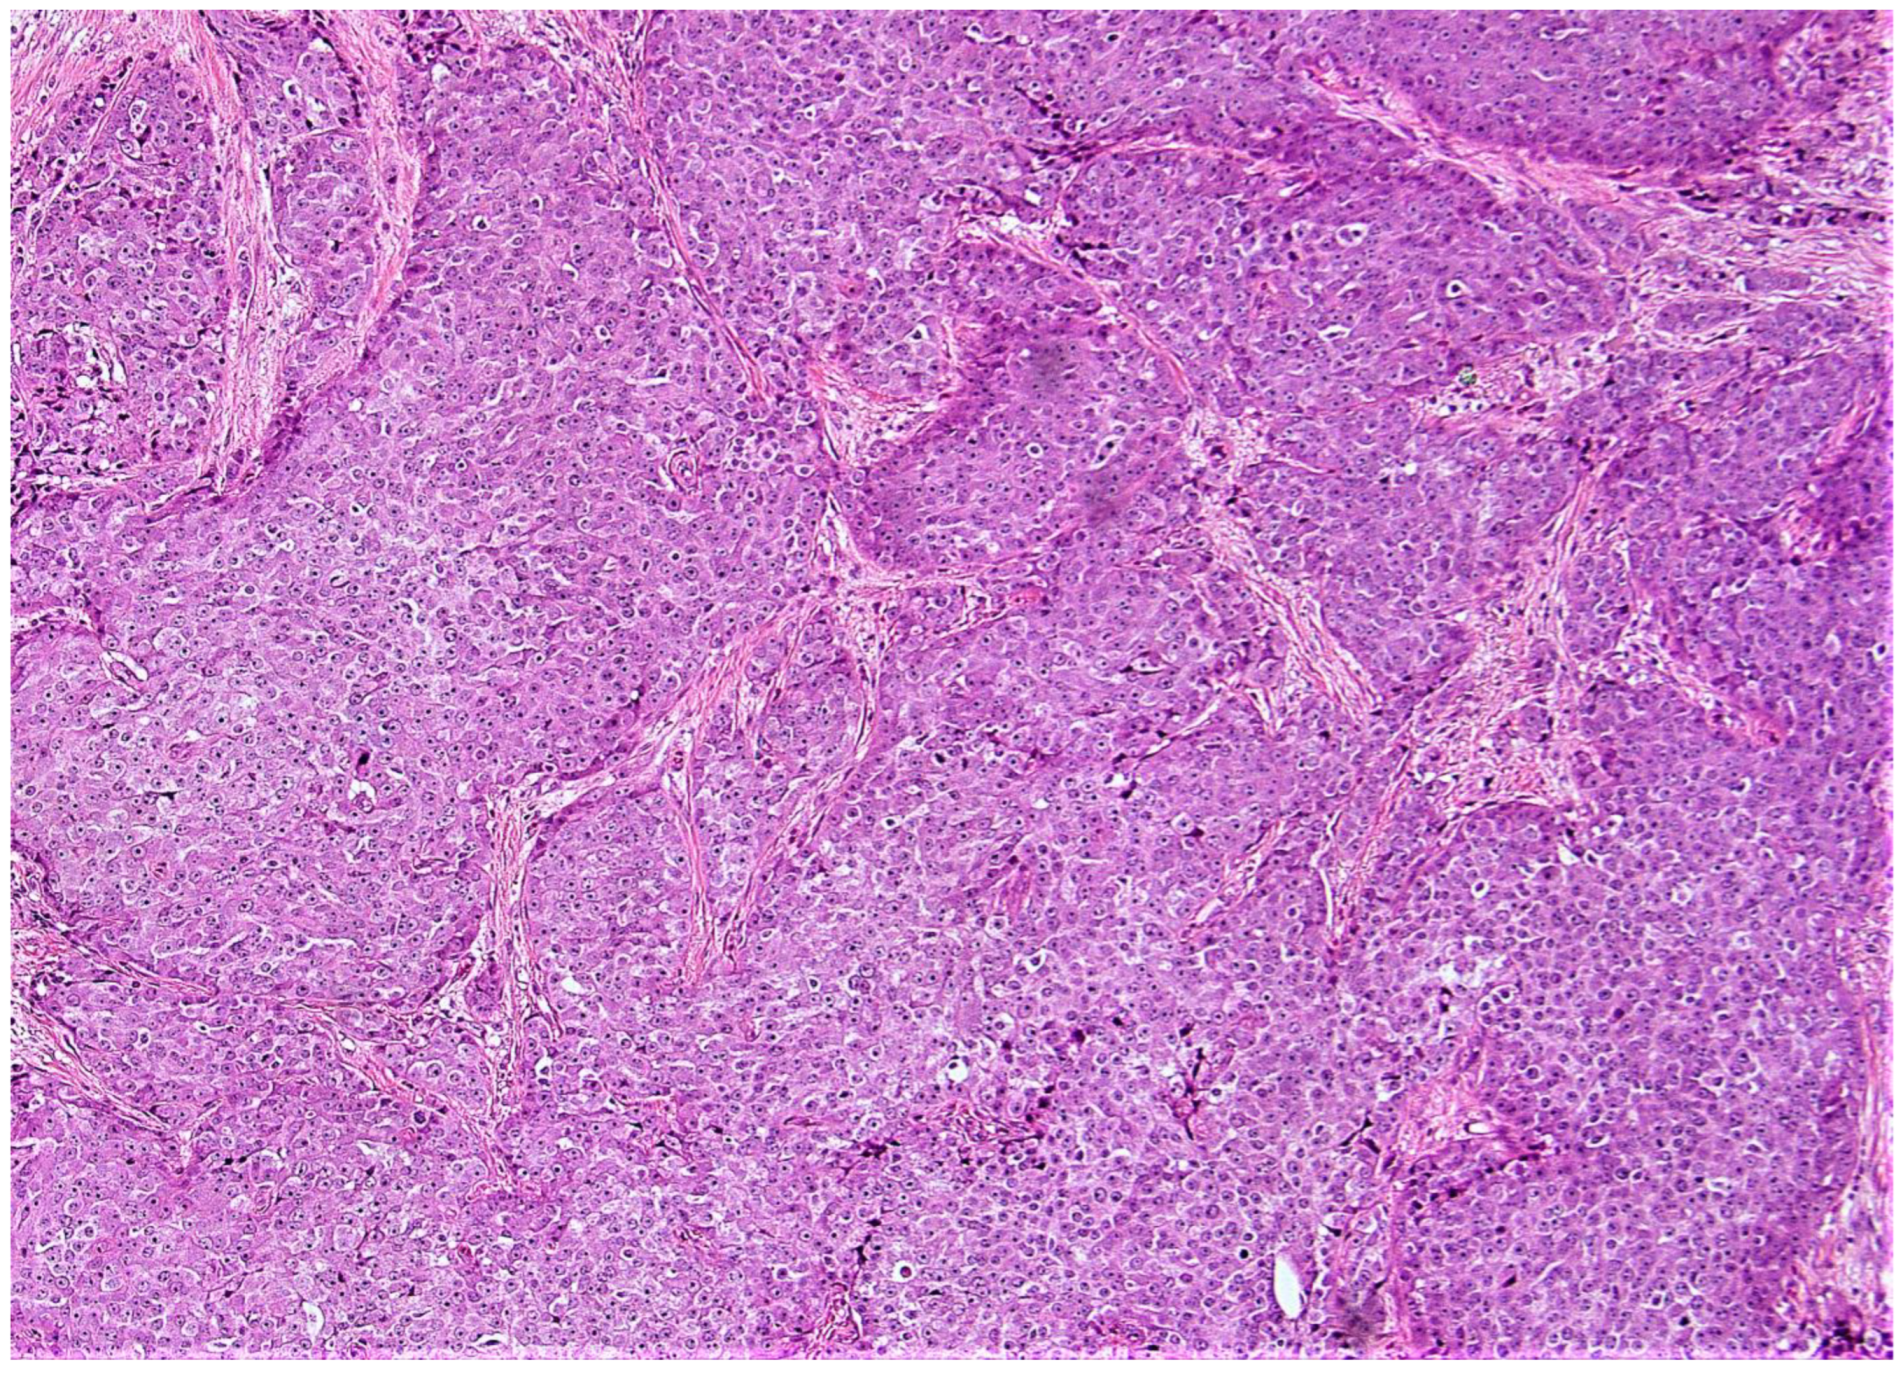

2. Materials and Methods

3. Results

4. Discussion